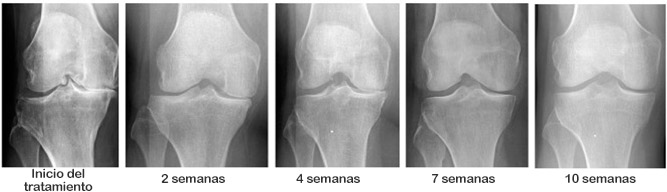

Julia comenzó a sentirse mejor cada día. Después de 7 días de tratamiento, fue al supermercado y compró algo de comida. En su rostro apareció esa sonrisa que tanto echaba de menos. 2 semanas más tarde, la artritis desapareció por completo. Parecía demasiado bueno para ser verdad, pero las pruebas mostraron que Julia estaba completamente sana, y yo estaba en el séptimo cielo. ¡Fue una verdadera victoria!

Llevamos tres meses distribuyendo Motion Energy. Esta oportunidad ya la aprovecharon varios miles de puertorriqueños. Les pedimos a todos los que recibieron Motion Energy que evalúen la eficacia del medicamento en una escala de 0 a 10. Por el momento, más de 3 600 personas participaron en la encuesta y la evaluación promedia del medicamento es 9.96 de 10

Como puede ver, ¡Motion Energy ayudó a devolver la movilidad y deshacerse del dolor a miles de puertorriqueños y casi gratis! Usted también puede estar entre ellos.